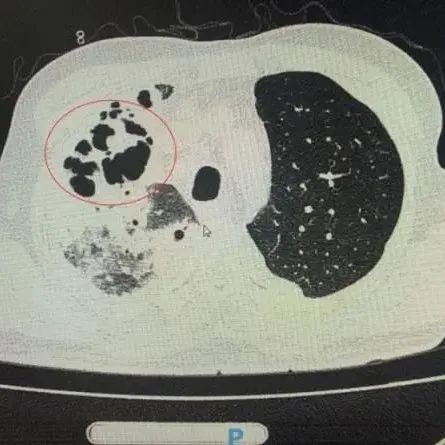

医学影像  yxyx-app  医学影像APP,打造伴随医生快速成长的影像学习社区。与影像园(Xctmr.com)一起提供最全面的影像案例库、基础(解剖、病理、影像诊断)知识、影像技术及考题等,为医生提供最佳的医学影像参考。【所属科室】呼吸科【基本资料】患者,男,60岁【主诉】反复咳嗽1月【影像图片】【讨论问题】如何诊断?【医学影像APP用户讨论】评论:左肺上叶肿块影,边界清,周围见少许磨玻璃影,其内可见液性密度,囊壁较厚,内缘光整,增强扫描囊壁明显强化,考虑脓肿可能大。...